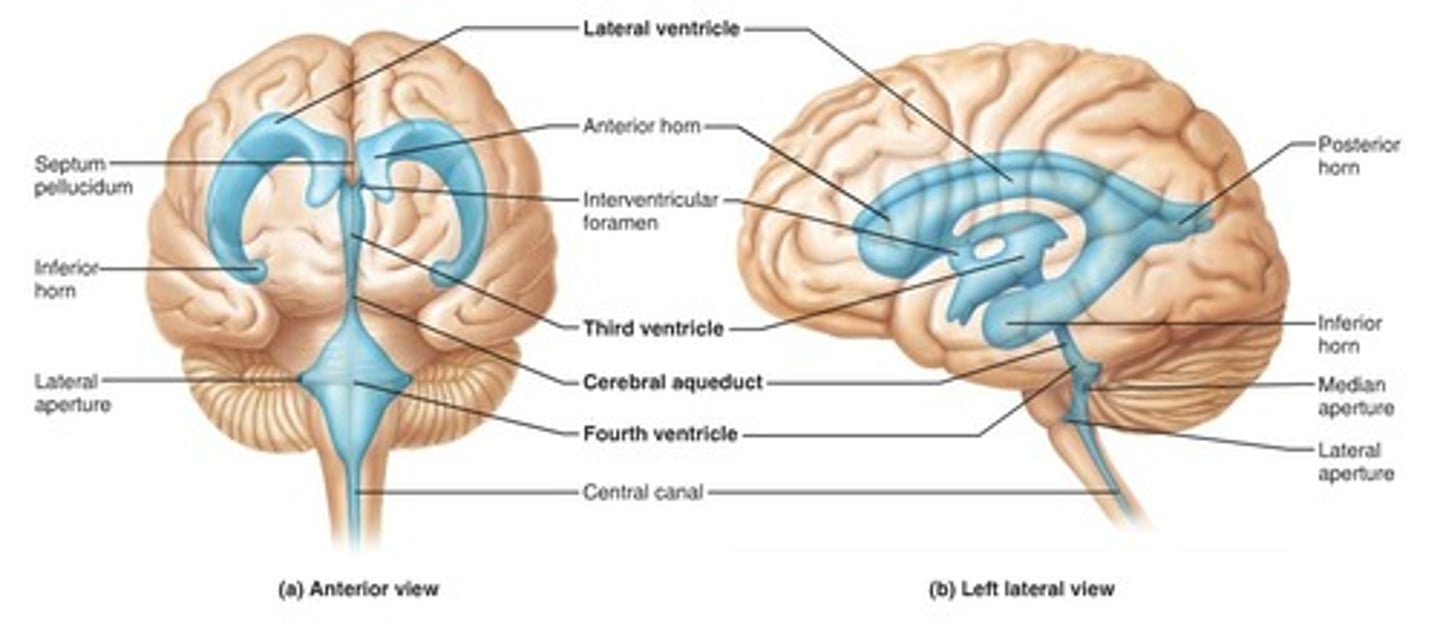

ventricles

cavities in the brain. Includes lateral ventricles - right and left, third ventricle, fourth ventricle, cerebral aqueduct, and choroid plexus.

lateral ventricles (left and right)

right and left. Actual open space. Behind the corpus collosum.

- Cerebrospinal fluid circulates through these ventricles and underneath the meninges.

- Gives the brain buoyancy.

- brain floats a little bit and this prevents trauma.

third ventricle

in the area where the hypothalamus is.

fourth ventricle

located beneath the arbor vitae in the cerebellum.

cerebral aqueduct

connector between third and fourth ventricle in front of colliculi.

choroid plexus

ependymal cells - line ventricles and central canal of spinal cord.